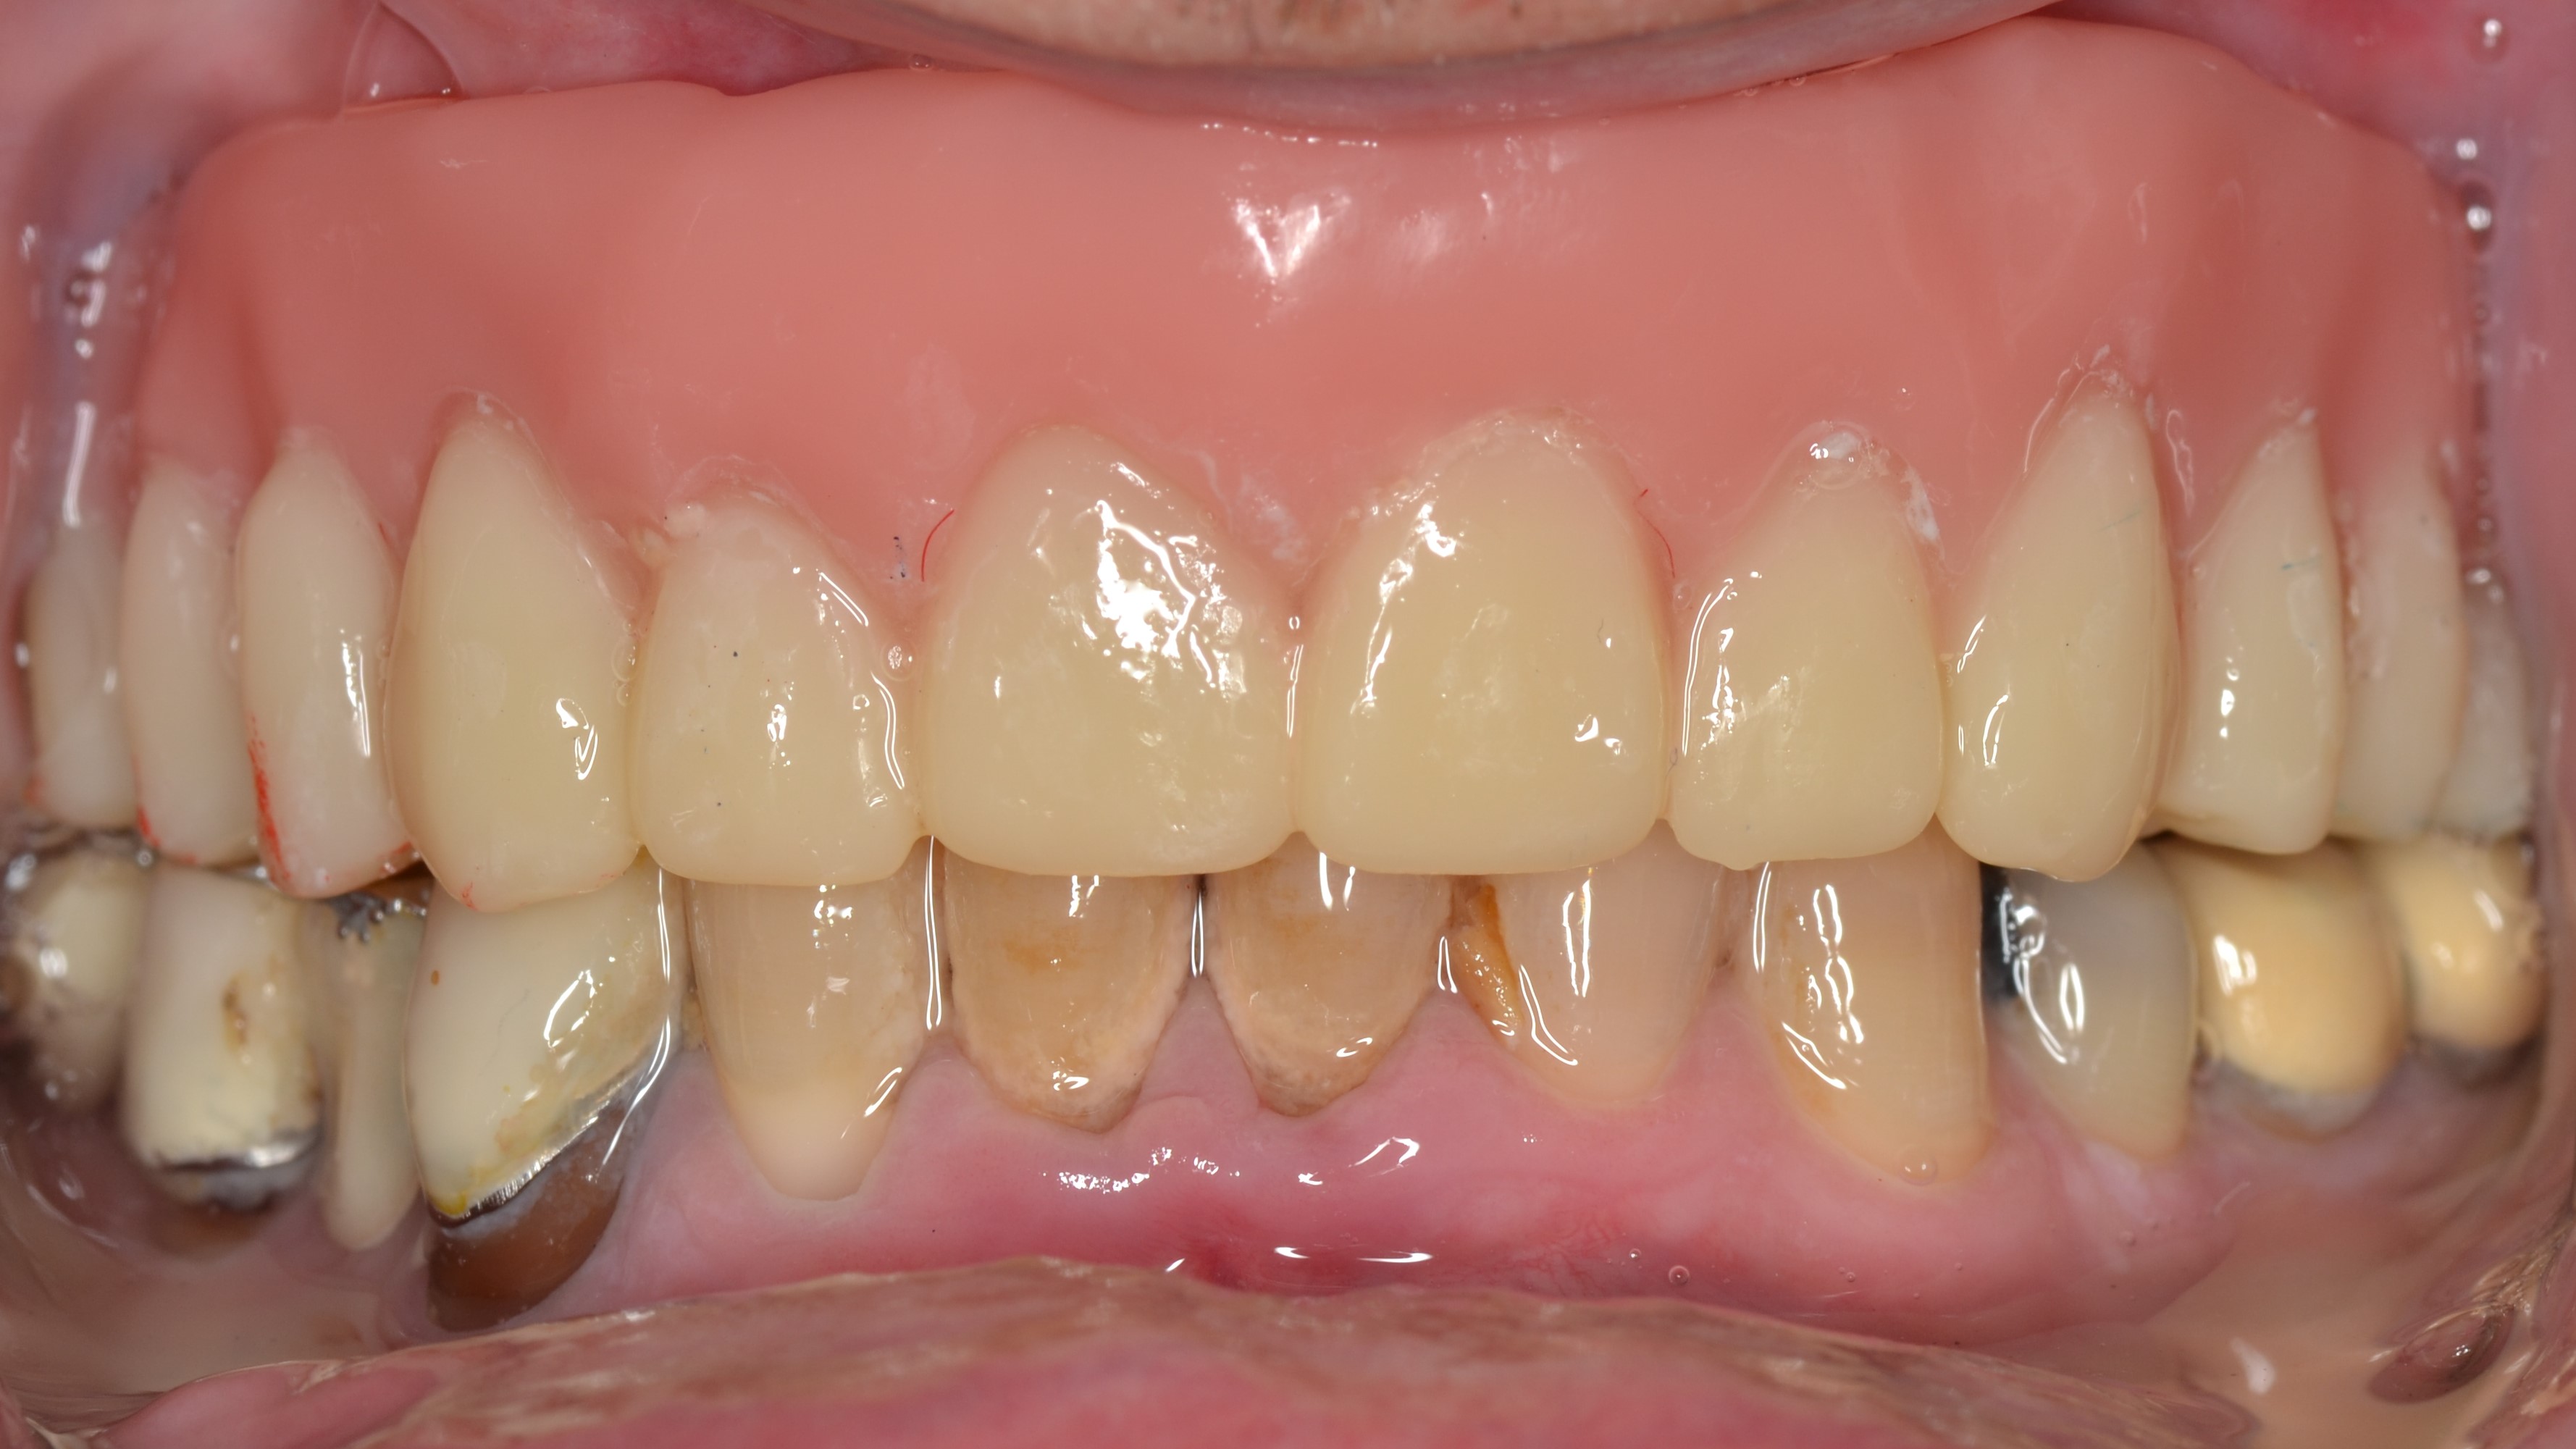

Ο ασθενής προσήλθε στο ιατρείο προκειμένου να βρει μια λύση για τα υπόλοιπα δόντια της άνω γνάθου που κουνούσαν και πονούσαν στην μάσηση.

Πάρθηκε ψηφιακό αποτύπωμα με τον σαρωτή TRIOS και μετά τις εξαγωγές των δοντιών, του κατασκευάσαμε μια ολική οδοντοστοιχία για να αποκαταστήσουμε τα δοντια που έλλειπαν.

Η βελτίωση στην αισθητική και στην λειτουργία του στόματος ενθουσίασε τον ασθενή μας.